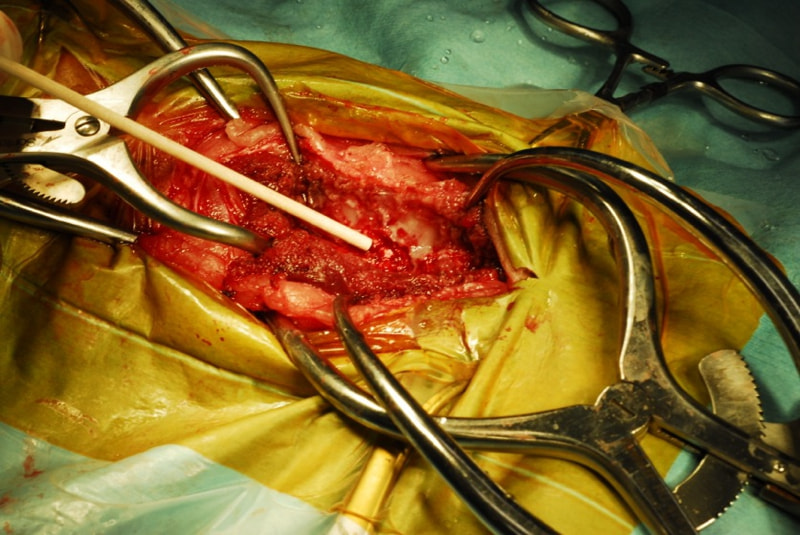

第4-5腰椎間、第5-6腰椎間の右側に片側椎弓切除術を実施しました。第5-6腰椎間の右神経根の腫瘤を切除、第五腰椎の硬膜切開を実施し、硬膜内-髄外の腫瘤を切除しました。

術中所見

神経根腫瘍